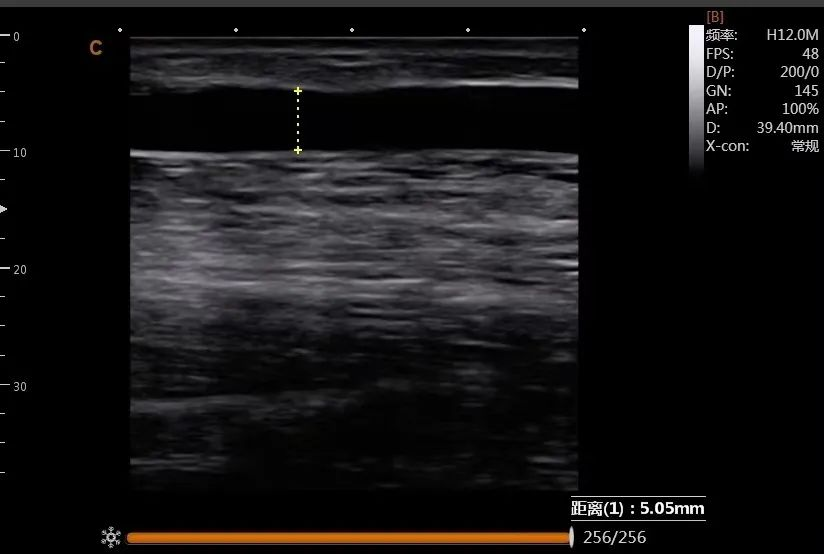

病例2:术后B超探查,动静脉内瘘流出道静脉内径为5mm